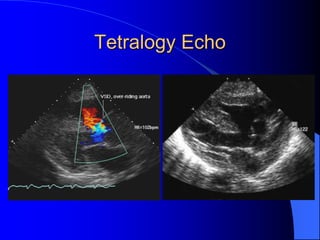

Tetralogy of Fallot

Echo

 Establishes diagnosis

 Determines severity of RVOT obstruction

 Flow across VSD

 Cardiac Cath

– Pressures, gradients, shunting, O2 sat, VSD

– Origins of coronary arteries

 Also seen by MRI or CTA

Tetralogy Echo

Tetralogy of Fallot Echo Establishes diagnosis  Determines severity of RVOT obstruction  Flow across VSD  Cardiac Cath – Pressures, gradients, shunting, O2 sat, VSD – Origins of coronary arteries  Also seen by MRI or CTA